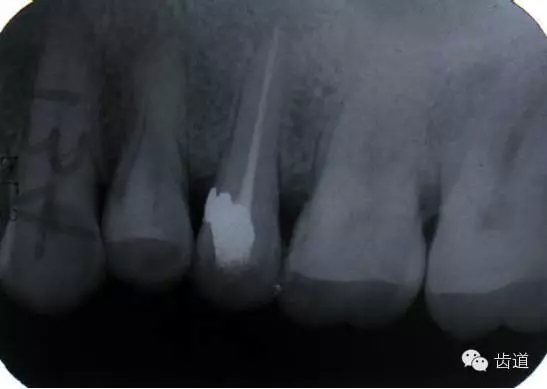

左上5牙頸部側穿

左上4鑄造樁側穿

左上7近中頰根器械折斷

右上6腭根器械折斷